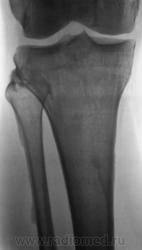

Мужчина средних лет, крепкий, ведущий активный образ жизни, занимающийся дозировано «элементами спорта», полковник милиции, в последнее время (несколько лет) почувствовал боли в области правого коленного сустава.

Энтезопатия надколенника, перегрузочная болезнь б/б кости(подозрение на неполный перелом).

Очень похожая картина на консолидированный перелом б\б кости. В проекции м\б кости определяется периостальная реакция или патологическая перестройка костной ткани.

Есть  признаки  артроза  и  синовита . Была  повреждена  передняя  крестообразная  связка.